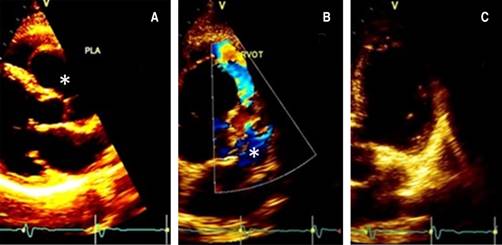

On physical examination, the blood pressure was 130/78 mmHg, heart rate 78 bpm, and no respiratory distress with a grade II/VI systolic ejection on the left upper sternal border, with normal pulses, without pericardial rub, jugular dilatation or paradoxical pulse. The echocardiogram revealed a mildly reduced Simpson’s rule calculated ejection fraction of 46% and inferolateral mild hypokinesis. The valvular examination revealed mild aortic and mitral insufficiency, dilated ascending aorta dimension at the sinus of Valsalva level, severe aneurysmal dilatation (2.5 × 4.6 mm) of a non-ruptured right sinus of Valsalva with right ventricular outflow tract compression and increased flow velocity in the pulmonary valve (Figure 2).

Figure 2: Doppler-echo pre-treatment; the asterisk shows the aneurysm in long (A) and short (B) parasternal and apical (C) view.